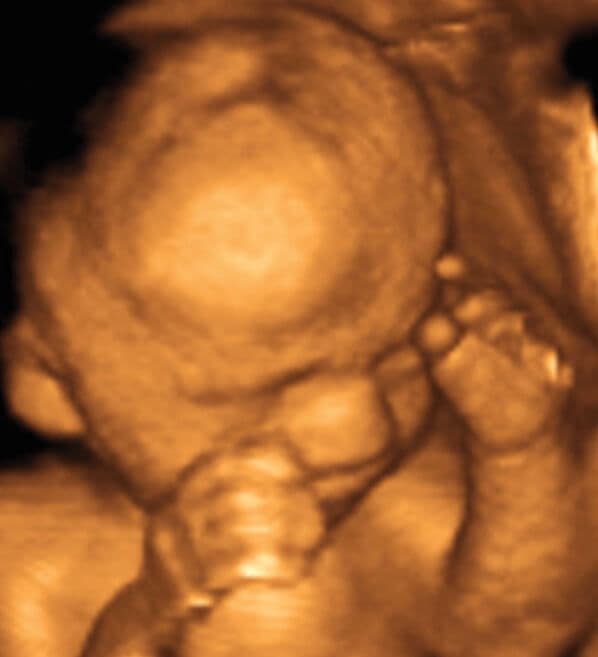

27 weeks and 6 days pregnant

Although ultrasound cannot show it, there is now some hair on your baby’s head and her eyelashes and eyebrows have grown. The pattern and colour of hair growth has a significant impact on the overall look of your baby but this is not apparent on a scan.